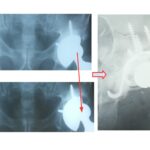

Στην εικόνα 3, ασθενής που κατά την αρχική της  επέμβαση υπέστη κάταγμα μηριαίου. Αντιμετωπίσθηκε λανθασμένα με τοποθέτηση συρμάτων τα οποία δε συγκράτησαν το κάταγμα. Λίγες εβδομάδες μετά, την αντιμετωπίσαμε με αναθεώρηση του μηριαίου στυλεού με ένα ειδικού τύπου μακρύ στυλεό και πολλαπλά σύρματα. 2 χρόνια μετά βαδίζει χωρίς ενοχλήματα.